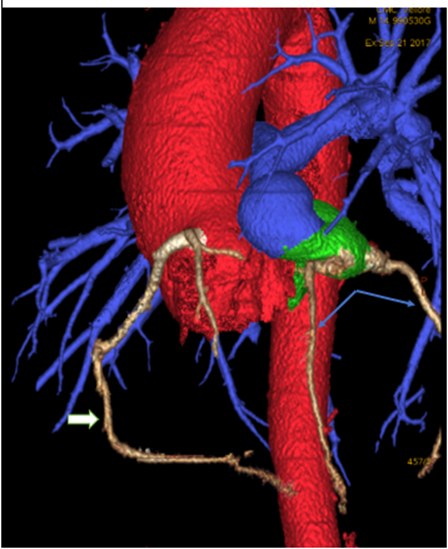

The right coronary artery (RCA) originates from the anterior and slightly left-facing sinus of the common trunk. Shortly after its origin, it gives rise to the infundibular branch and then continues along the atrioventricular groove. At the inferior portion of this groove, it gives off the acute marginal branch, which runs along the free wall of the right ventricle. The posterior descending artery (PDA) also arises from the RCA.

The left anterior descending (LAD) and left circumflex (LCx) arteries originate from the main pulmonary trunk and follow their normal anatomical courses. The LAD exhibits a Type 3 course. (Figure 4)

Figure 4: The right coronary artery (RCA) originates from the anterior and slightly left-facing sinus of the common trunk (White arrow). The left anterior descending (LAD) and left circumflex (LCx) arteries originate from the main pulmonary trunk and follow their normal anatomical courses. (Blue arrow)